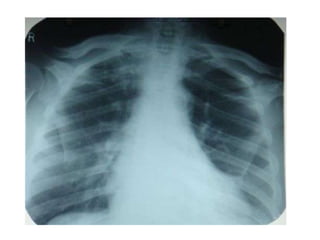

Normal Chest X-Ray

Scheme of viewing PA film